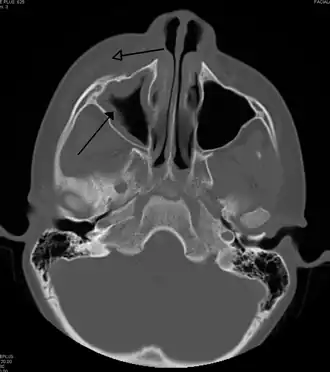

![]() Периорбитальный целлюлит, вызванный стоматологической инфекцией (которая также приводит к верхнечелюстному синуситу)) | |

Периорбитальный целлюлит необходимо дифференцировать от орбитального целлюлита, который является чрезвычайной ситуацией и требует внутривенного введения (IV) антибиотиков. В отличие от орбитального целлюлита, у пациентов с периорбитальным целлюлитом отсутствуют выпуклые глаза (экзофтальм), ограниченное движение глаз (офтальмоплегия), боль при движении глаз, или потеря зрения. Если какой-либо из этих признаков присутствует, надо полагать, что пациент имеет орбитальный целлюлит и начать лечение IV антибиотиками. КТ-сканирование может быть сделано, чтобы очертить расширение инфекции.